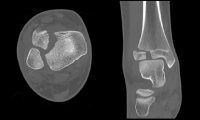

A 45-year-old male slips on a sidewalk. He has mild lateral pain, his medial malleolus is non-tender, and he is non-weight-bearing. The OAR indicated X-rays, and the emergency department images are above (Case 2, Figure 1).

The emergency department report showed the patient had mild tenderness laterally and no tenderness over the medial malleolus. He was diagnosed with a STI of the ankle, placed in an air-stirrup, given crutches, and provided with follow-up in the clinic in a week.

He came back on day 10. He was quite specific about the mechanism. He caught the instep of his right foot, and as his left foot went forward, his injured right foot clearly turned out. The mechanism was external rotation, a red flag mechanism. He was unable to bear weight up. At the patient’s follow-up exam, the emergency physician stated, “The patient had very mild tenderness laterally, and he was non-tender over the medial malleolus.” However, as images Case 2, Figure 3A–C show, he also had pain at three other points (points the OAR do not ask us to examine).

In the clinic on day 10, X-rays were taken of the tibia and fibula (Case 2, Figures 4A and 4B). The proximal fibula shows the oblique fracture of the fibula. The fracture is only seen on the lateral view (Case 2, Figure 4B), a reminder of the orthopedic mantra, “One view is one view too few.” He had the classic Maisonneuve fracture, an external rotation mechanism resulting in injuries to the medial ankle (deltoid ligament or medial malleolus), syndesmosis, and interosseous membrane exiting out the proximal third of the fibula with an oblique fracture.

The patient was referred to an orthopedic surgeon and had surgery the following day, as shown in Case 2, Figure 2.

The OAR ask us to examine the posterior 6 cm of the medial and lateral malleoli, which was done. However, that is not a complete emergency department ankle exam. One needs to palpate many structures to localize the pain and discover the pathology. In this case, the ankle exam also revealed pain over both the deltoid ligament and the syndesmosis. Neither of these are part of the OAR. Either one can be a red flag on physical, and the combination certainly is concerning for a higher fibular fracture, which on palpation can be quite subtle. So in cases of twisting ankle injuries with significant medial ankle pain and little or no lateral ankle pain, it is best to X-ray the ankle and add the tibia/fibula views as a separate X-ray study.

This case again highlights that the OAR are not a complete emergency department ankle exam; they are simply a tool to use after a proper ankle assessment to decide if an X-ray is indicated.

It can be a bit daunting to see the “normal” X-rays and then the intraoperative films. This case was a missed Maisonneuve fracture, a classic fracture that will often show up on board certification examinations. More important than nailing the exam question, we should make sure we know how to recognize it the next time we see an emergency department patient with an ankle injury. This was a very subtle case without medial malleolus fracture (he had the deltoid ligament equivalent) and without shift of the ankle mortise. If we mistakenly put all of our focus on the X-ray, we are more likely to miss uncommon injuries. Again, the importance of history, appreciating that external rotation is a red flag, and physical tenderness over the deltoid ligament and the syndesmosis cannot be overemphasized. Then interpret the X-ray in the proper clinical context.